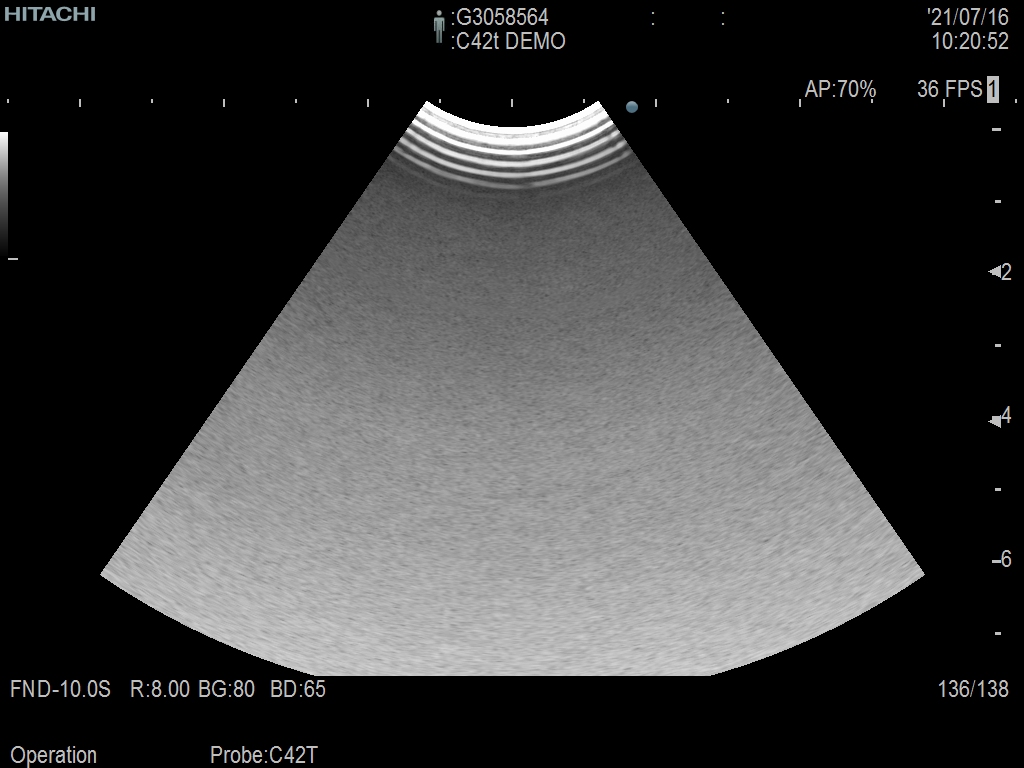

Hitachi C42T Ref Intraoperative Convex – ARIETTA

ARIETTA Convex C42T Intraoperative

Intraoperative Finger-grip T-Style

10 – 3 MHz

Hitachi C42T Intraoperative Convex – ARIETTA

Frequency Range: 10 – 3 MHz

Scan Width: 20 mm Radius

Scan Angle: 65° FOV

Hitachi C42T Intraoperative Convex – ARIETTA for Intraoperative Finger-grip Convex T-Style